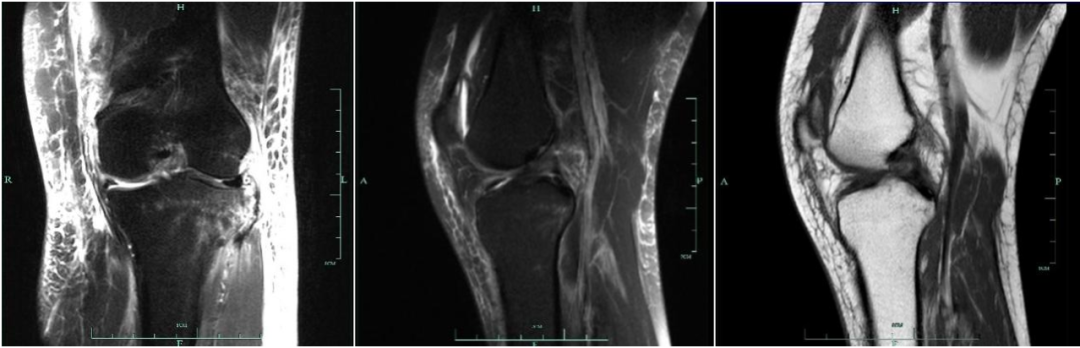

女,65 岁,左膝关节前交叉韧带损伤,膝关节积液,T1 及 T2 加权序列前交叉韧带信号增高,但韧带纤维束完整外形无明显改变

女,54 岁,左膝关节前交叉韧带部分撕裂,左侧胫骨上段骨折伴骨髓水肿,矢状面 T1 加权序列,冠状面及矢状面 T2 加权序列,韧带信号增高,部分纤维束连续

女,40 岁,外伤 2 周,前交叉韧带胫骨附着部撕脱骨折,胫骨平台骨折,胫骨平台骨折,胫骨见骨折线,伴骨髓水肿,韧带信号明显增强且不连续为 3 级损伤;髌腱远端见高信号改变